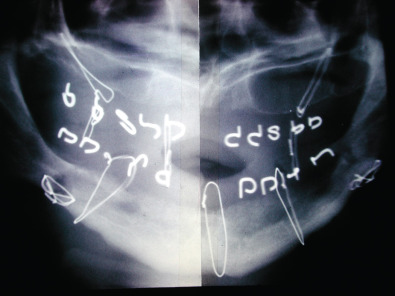

If maxillofacial trauma is suspected, radiographs will most likely be performed. Plain films of the maxillofacial region such as the mandible series, Waters view and submental vertex view are almost always now being replaced by the computed tomography (CT) scan. CT scans of the maxillofacial region give much better detail in a 3-dimensional aspect to assist the provider in diagnosing the injury and formulating a treatment plan. Occasionally, patients seen in the outpatient office will have an orthopantomogram (panorex) as a screening film for mandibular trauma. The orthopantomogram should have another radiograph in a second plane such as an AP film or CT scan to fully assess the injury. A CT scan is the optimal study to assess maxillary and upper face trauma. Additionally, the CT scan can be carried through the skull to assess bony and soft tissue injuries to the central nervous system and cervical spine ( Figs. 1.21.3–1.21.6 ).

Historically, edentulous mandible fractures were treated by closed reduction. This required altering the patient’s denture and fixating the dental prostheses to the patient’s jaws and using postoperative maxillomandibular fixation (MMF). Alternatively, dental splints could be fabricated and secured to the patient and postoperative maxillomandibular fixation could be used. The dental splints could be one- or two-piece constructs. The one-piece constructed dental prosthesis is known as the Gunning splint. Treating edentulous mandible fractures with dental prostheses required additional knowledge not available to all surgeons managing facial fractures. A dental laboratory facility needed to be available in order to fabricate the acrylic prostheses after dental models had been obtained. This could be cumbersome, time-consuming and delay patient care. Additionally, the patient’s postoperative course was very difficult because of the dental appliances fixated to their jaws and the postoperative MMF. External fixators have also been used to stabilize edentulous mandible fractures as there are no teeth present. Precise anatomical reduction is often difficult with external fixators, especially in the atrophic mandible fracture with reduced bone stock. Management of edentulous mandible fractures by closed reduction techniques was difficult for the patient and had a high complication rate of nonunion ( Figs. 1.21.7–1.21.11 ).